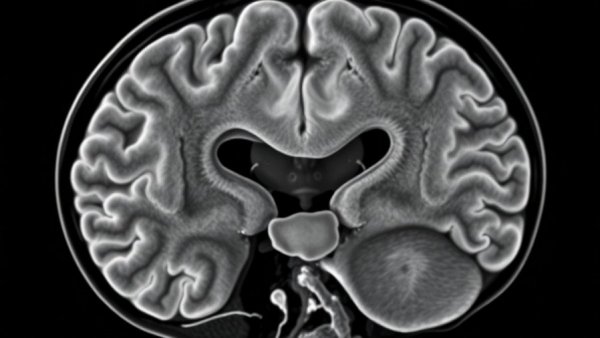

Grayscale MRI image of brain showing meningioma, highlighting Childhood Cancer Survivors Meningioma Risk.

The journey of childhood cancer survivors does not end upon recovery from their primary disease; rather, it continues with the lurking shadow of potential long-term health complications. A recent study revealed concerning statistics regarding the lifetime risk of meningioma, a type of brain tumor, among these survivors. Specifically, a 35-year cumulative incidence of 2.3% was observed, underscoring a critical need for ongoing surveillance in this unique patient population.